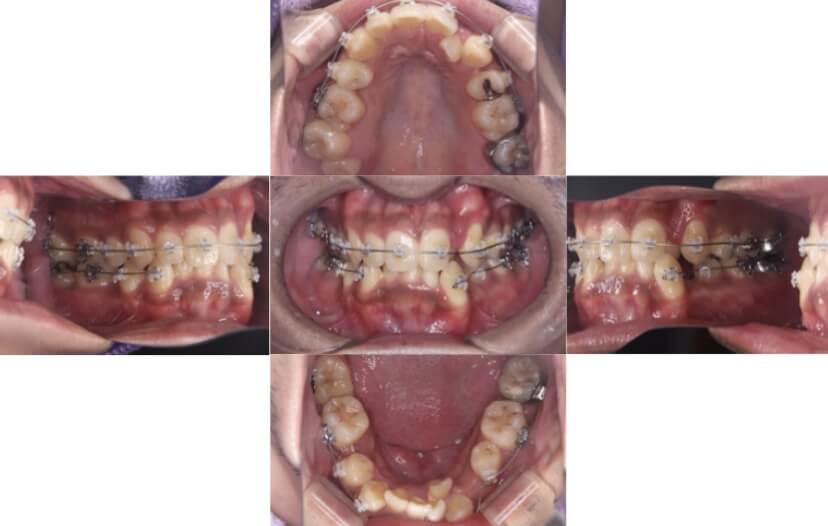

BEFORE

治療経過

上下顎叢生(上下の前歯のガタガタ)のケースです。

装置はラビアル(上下表側)で、上下顎の小臼歯を4本抜歯を行っています。抜歯したスペースを使って、上下の前歯の後方移動と叢生(ガタガタ)の改善を行っています。

主訴 歯並びが悪く、舌を噛んでしまうのを治したい。

年齢・性別 27歳 男性

お住まいの地域 東京都大田区

治療方針 抜歯スペースを利用して上下前歯の叢生(ガタガタ)の改善

抜歯部位 上下顎左右第一小臼歯

使用装置 ラビアル(上下表側)、顎間ゴム

治療期間 3年1か月

治療回数 30回

リテーナー クリアリテーナー